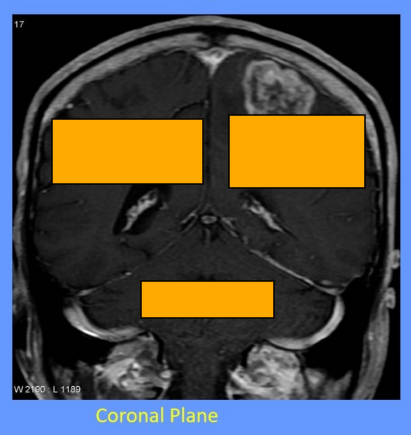

What is the tentorium cerebelli and what does it do

tent shaped fold of dura mater

divides the intracranial cavity into supratentorial and infratentorial compartments

What divides the supratentorial compartment

divided by the falx cerebri into the left and right supratentorial space which can communicate with each other and with the infratentorial space

What is the falx cerebri

vertical fold of the dura mater located in the longitudinal fissure that separates the left and right cerebral hemispheres